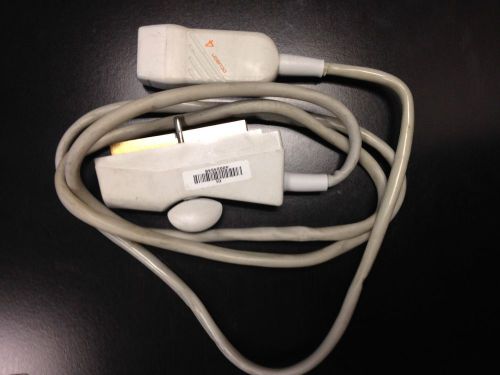

ACUSON V4 Ultrasound Needle Guide Transducer Probe-sn: 40032227

ACUSON V4 ULTRASOUND NEEDLE GUIDE TRANSDUCER PROBE-SN:40032227

ACUSON V4 Ultrasound Needle Guide Transducer Probe-sn: 40024548

Acuson C3 Needle Guide Prob SN:53307951